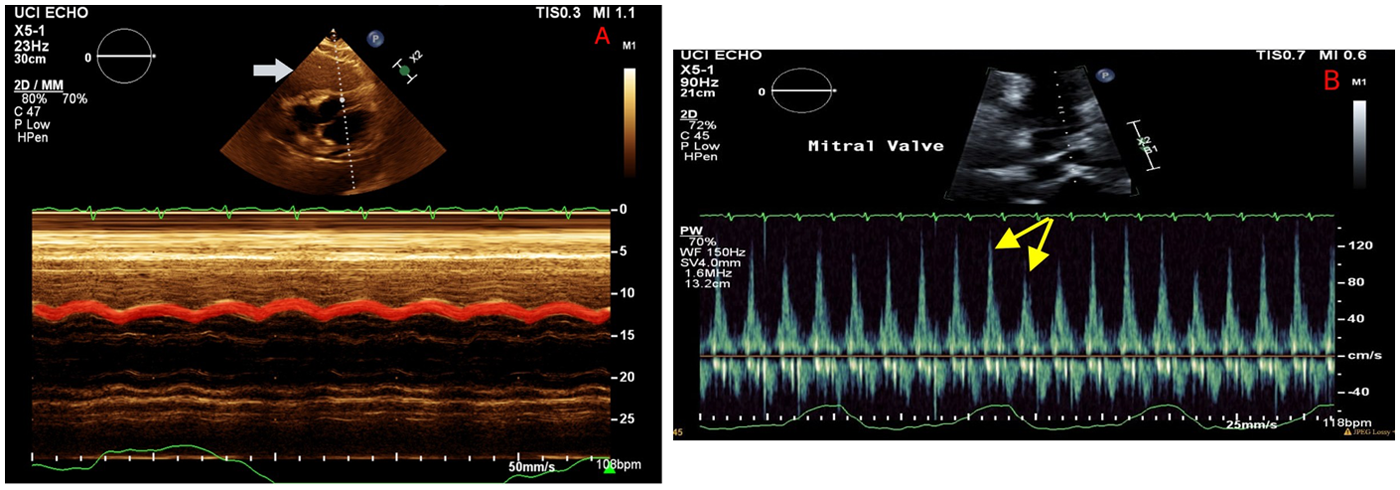

On hospital day 2, the patient developed worsening tachycardia and respiratory distress. Physical examination noted a tachycardia rate of 130 bpm with clear heart sounds and a blood pressure of 101/68 mmHg; JVD was present, and pulsus paradoxus was appreciated with a respiratory variation of systolic blood pressure (SBP) >20 mmHg. Repeat CT showed interval enlargement of the mediastinal mass with right atrial and RV compression, significant narrowing of the main pulmonary arteries, and compression of the superior vena cava (Figure 2). Repeat echocardiogram showed minimal reaccumulation of pericardial fluid but redemonstrated the large mediastinal mass, with compression of the right ventricle causing significant respiratory inflow variability in the mitral valve (40%), tricuspid valve (30%), and aortic valve (20%) spectral Doppler velocities with septal bounce that was concerning for tamponade physiology (Figure 3). He was resuscitated with 1 L of lactated Ringer's solution and brought to the ICU for stabilization. Conservative measures were unsuccessful in reversing his respiratory distress, which was thought to be secondary to a combination of imminent tamponade, pulmonary artery compression, and significant left lung atelectasis due to compression from the space-occupying lesion. Increasing oxygen requirements and respiratory fatigue prompted intubation and mechanical ventilation. The decision-making process involved cardiothoracic surgery, which deemed the patient to be a poor surgical candidate because of the unacceptable risk of cardiopulmonary collapse with general anesthesia.

Figure 3

Echocardiography on hospital day 2 illustrating a large mass abutting the right ventricle (A, white arrow), with M mode demonstrating a diastolic collapse of the right ventricular wall (red highlight). Mitral valve Doppler (B) showing persistent respiratory variation of mitral valve inflow (yellow arrows), consistent with recurrent tamponade physiology despite resolution of the pericardial effusion.